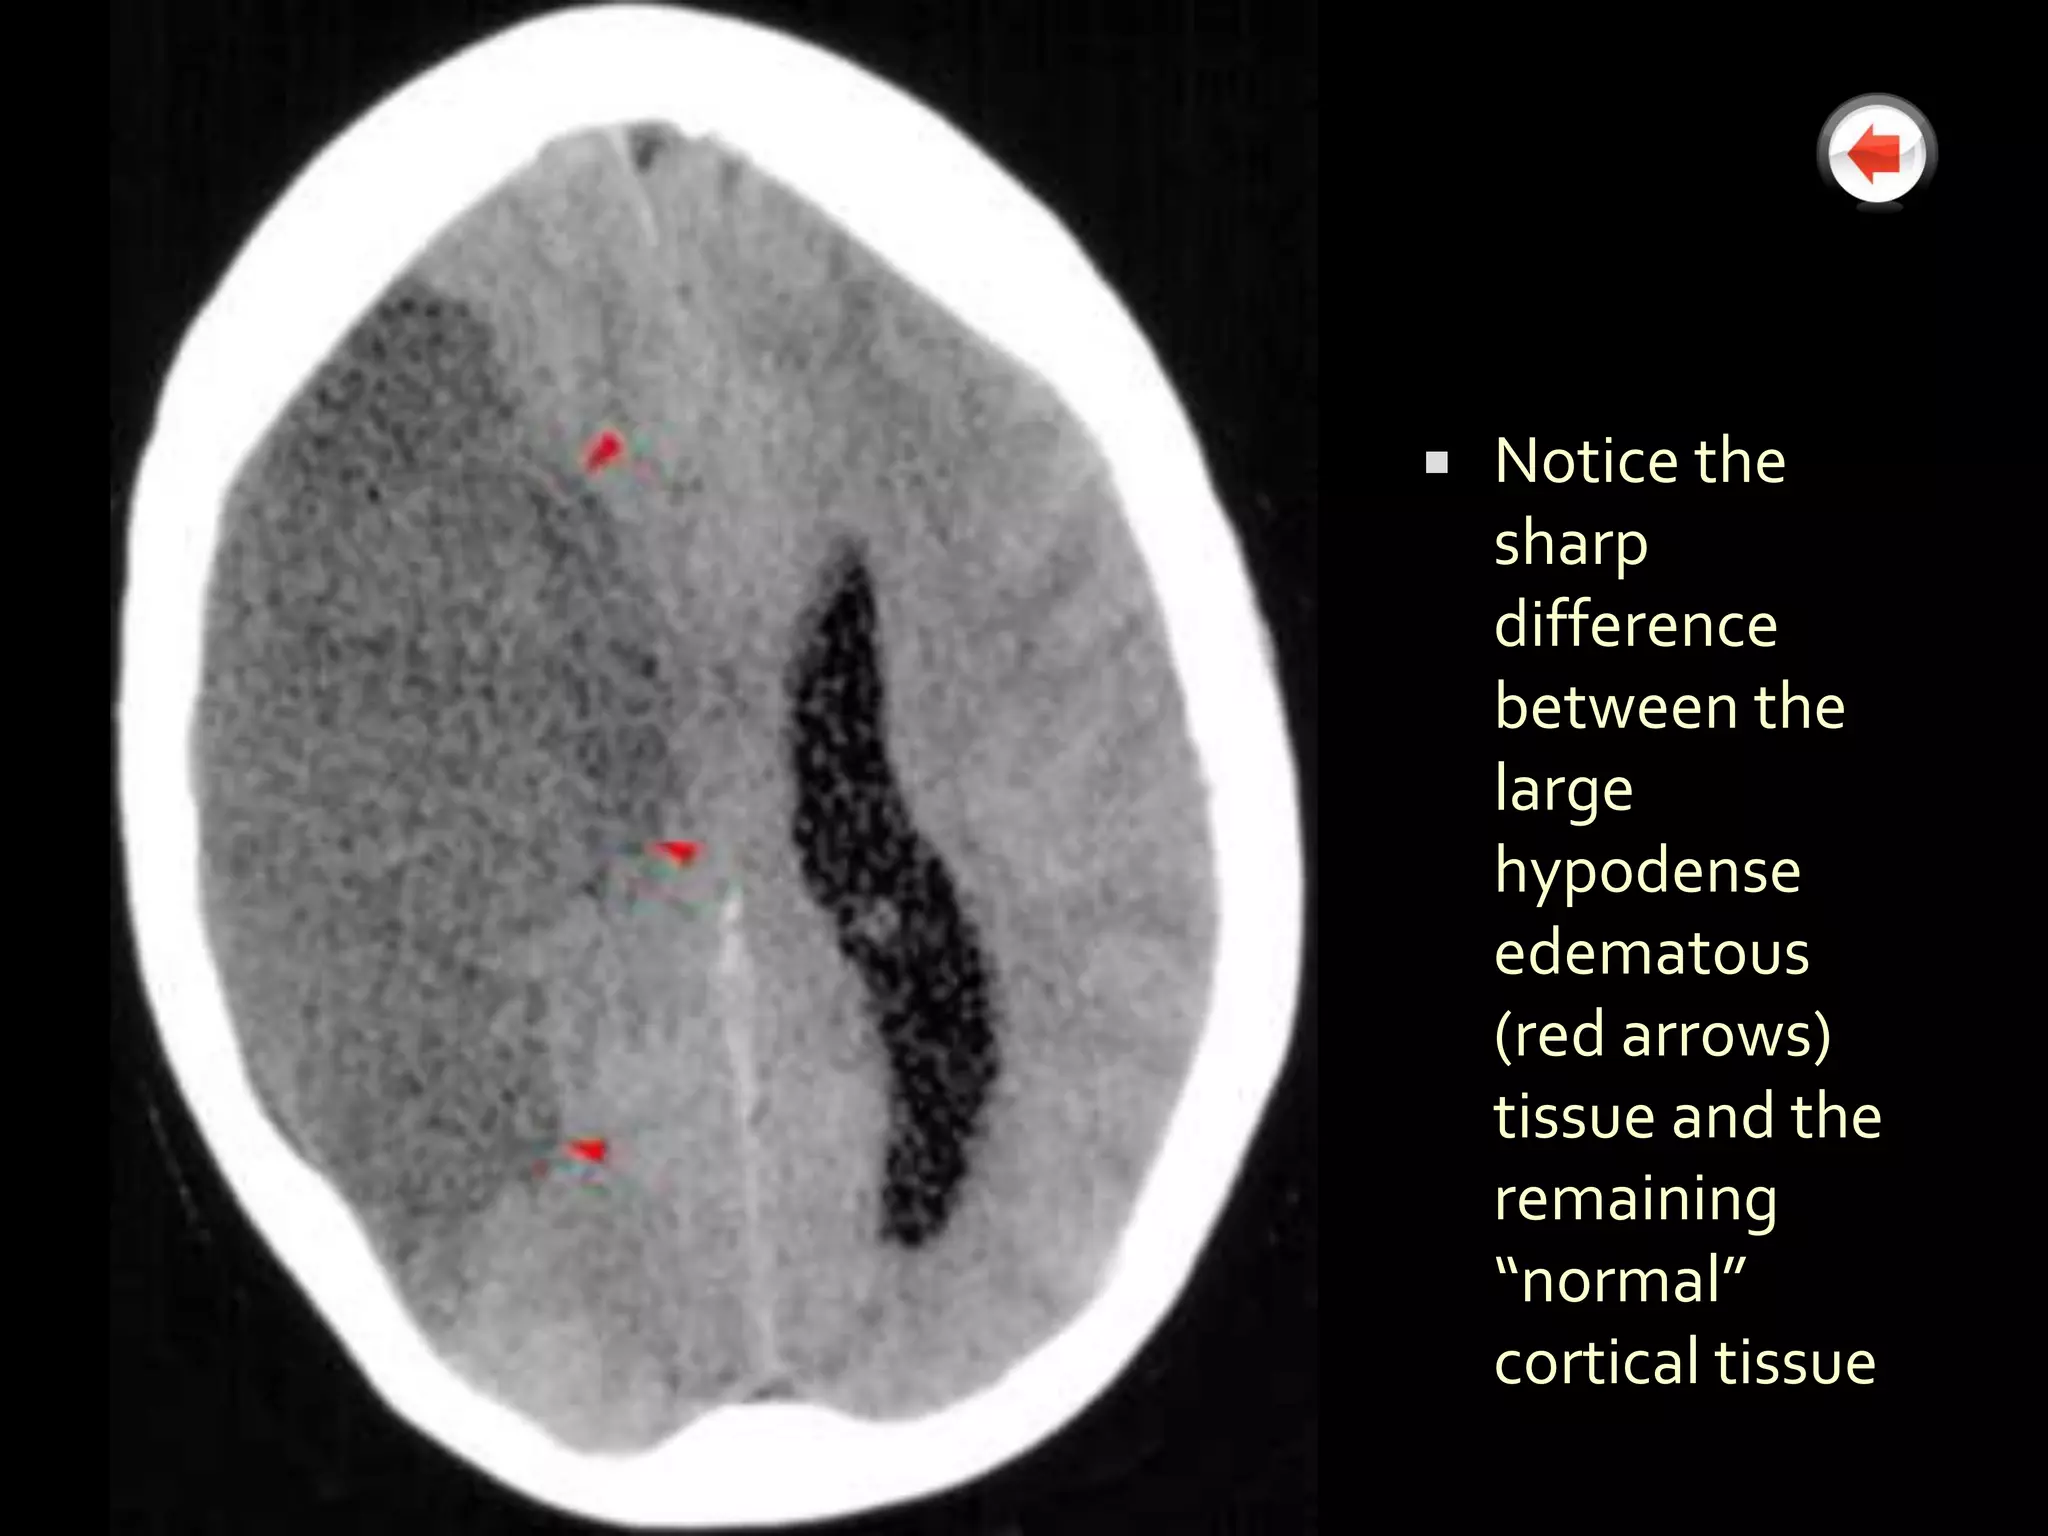

   Notice the

sharp

difference

between the

large

hypodense

edematous

(red arrows)

tissue and the

remaining

“normal”

cortical tissue

Used with permission by the CRASH Trials with credit to Mr. J. Wasserberg and Mr. B. Mitchell